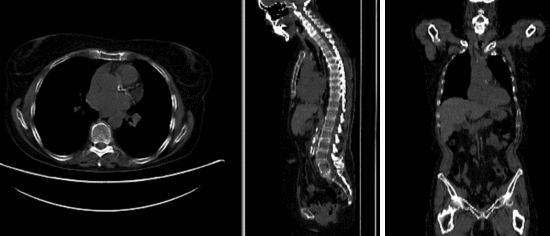

• reference/fixed : baseline CT: 0.98 x 0.98 x 5 mm , 512 x 512 x 149; PET: 4.1 x 4.1 x 5 mm , 168 x 168 x 149

• moving: CT: 0.98 x 0.98 x 5 mm , 512 x 512 x 149; PET: 4.1 x 4.1 x 5 mm , 168 x 168 x 149

Registration Results